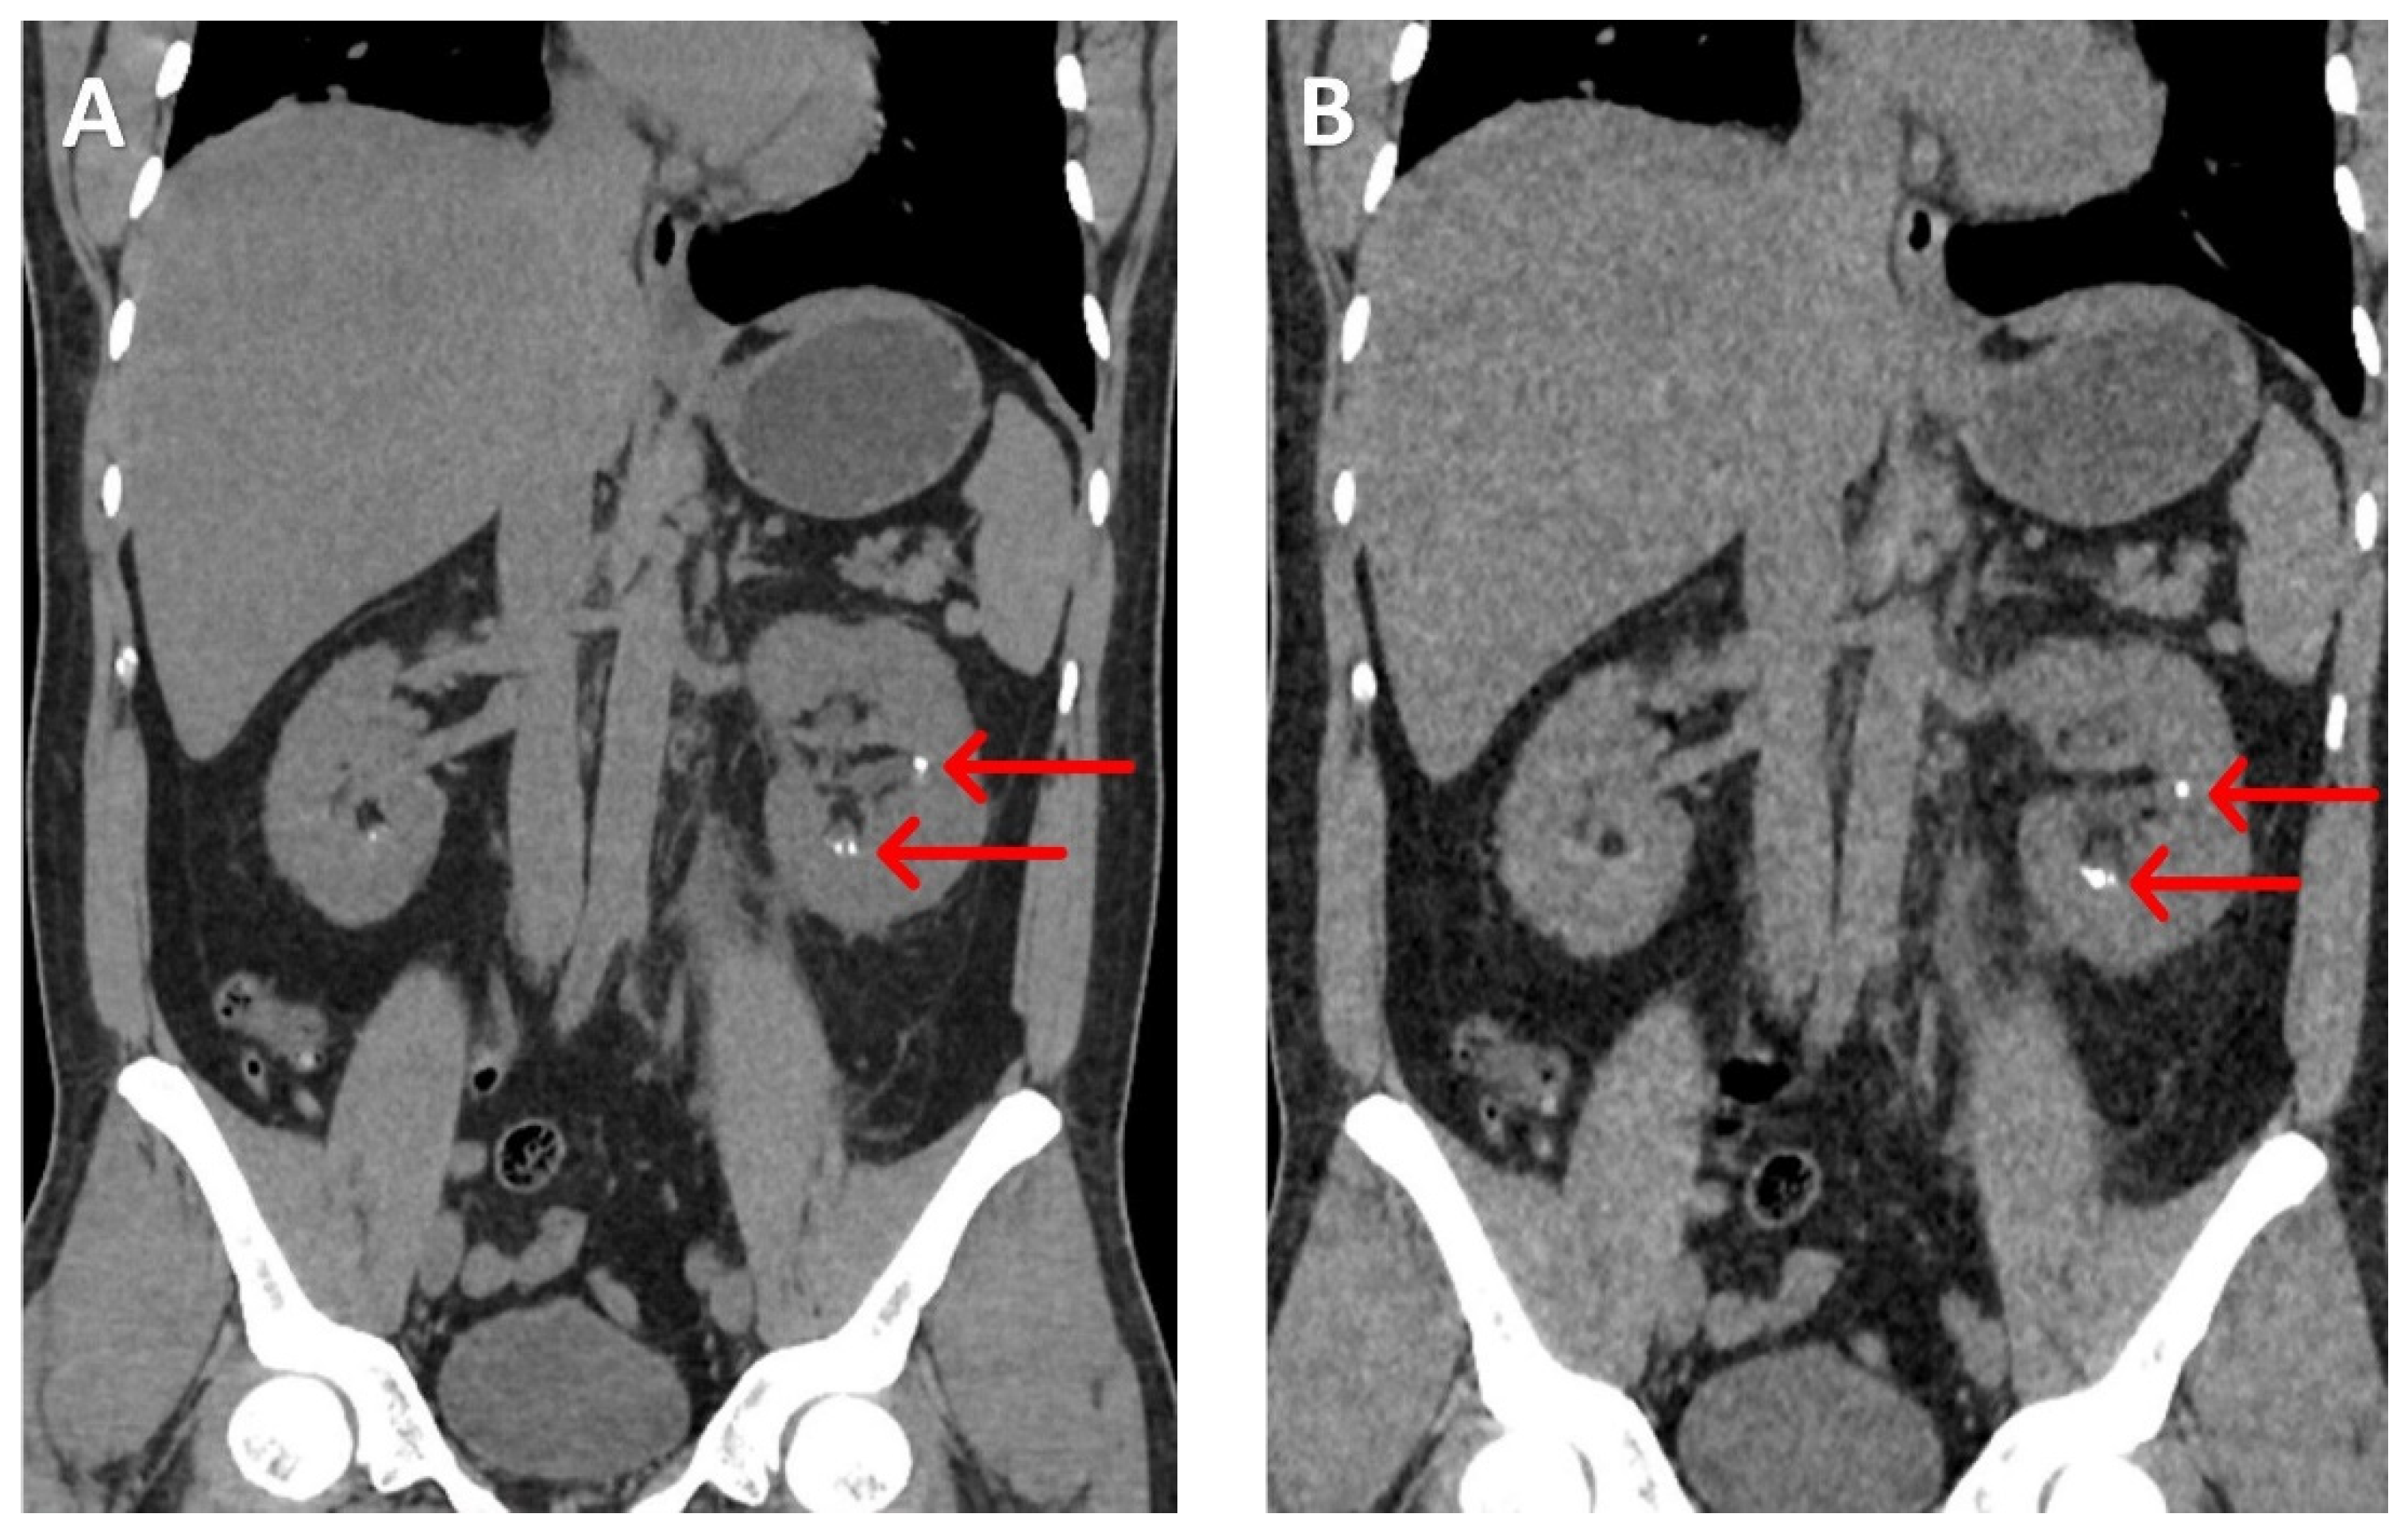

A meta-analysis has shown that LDCT-KUB can detect renal calculi > 3 mm with a sensitivity of 93% and specificity of 97%, using an average radiation dose of 1.4 mSv. This represents an approximately 85% reduction in radiation compared to the standard-dose CT-KUB (22) (Figure 1 and Figure 2).

Figure 2. A patient with calculus in right side utero-vesicular junction( 9 mm 5.1 mm /density:1050 HU. A: Normal dose CT -KUB with effective dose is 19.8 mSv. B: The low-dose protocol, with an effective dose of 2.6 mSv, shows the same calculi with good resolution.